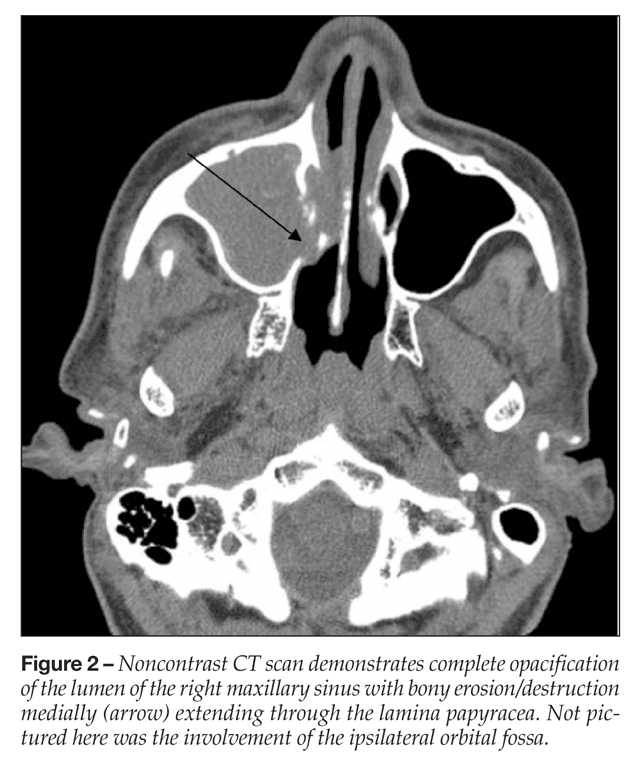

Noncontrast CT scans commonly demonstrate hypoattenuating mucosal thickening or soft tissue attenuation within the lumen

of the sinus, with predilection for unilateral involvement of the ethmoidal and sphenoidal sinuses. Bony erosion and mucosal thickening can be absent early in the disease course (Figure 2).30 Fungal sinusitis can demonstrate hypointensities within the sinuses on MRI T1-weighted sequences, and in Aspergillus sinusitis, concentrations of ferromagnetic ions exert a paramagnetic effect, accentuating this finding. While CT of the sinuses is more sensitive for bony changes, MRI provides superior evaluation of intracranial and intraorbital extension of disease and should be included as part of the initial evaluation.31 IFS is confirmed by both radiographic and histopathological evaluations.32 Surgically resected tissue often demonstrates considerable necrosis, edema, acute inflammation, and angioinvasion. In one series, CT scans were normal in 12% of patients with IFS; therefore, imaging cannot replace careful endoscopic evaluation and biopsy.33